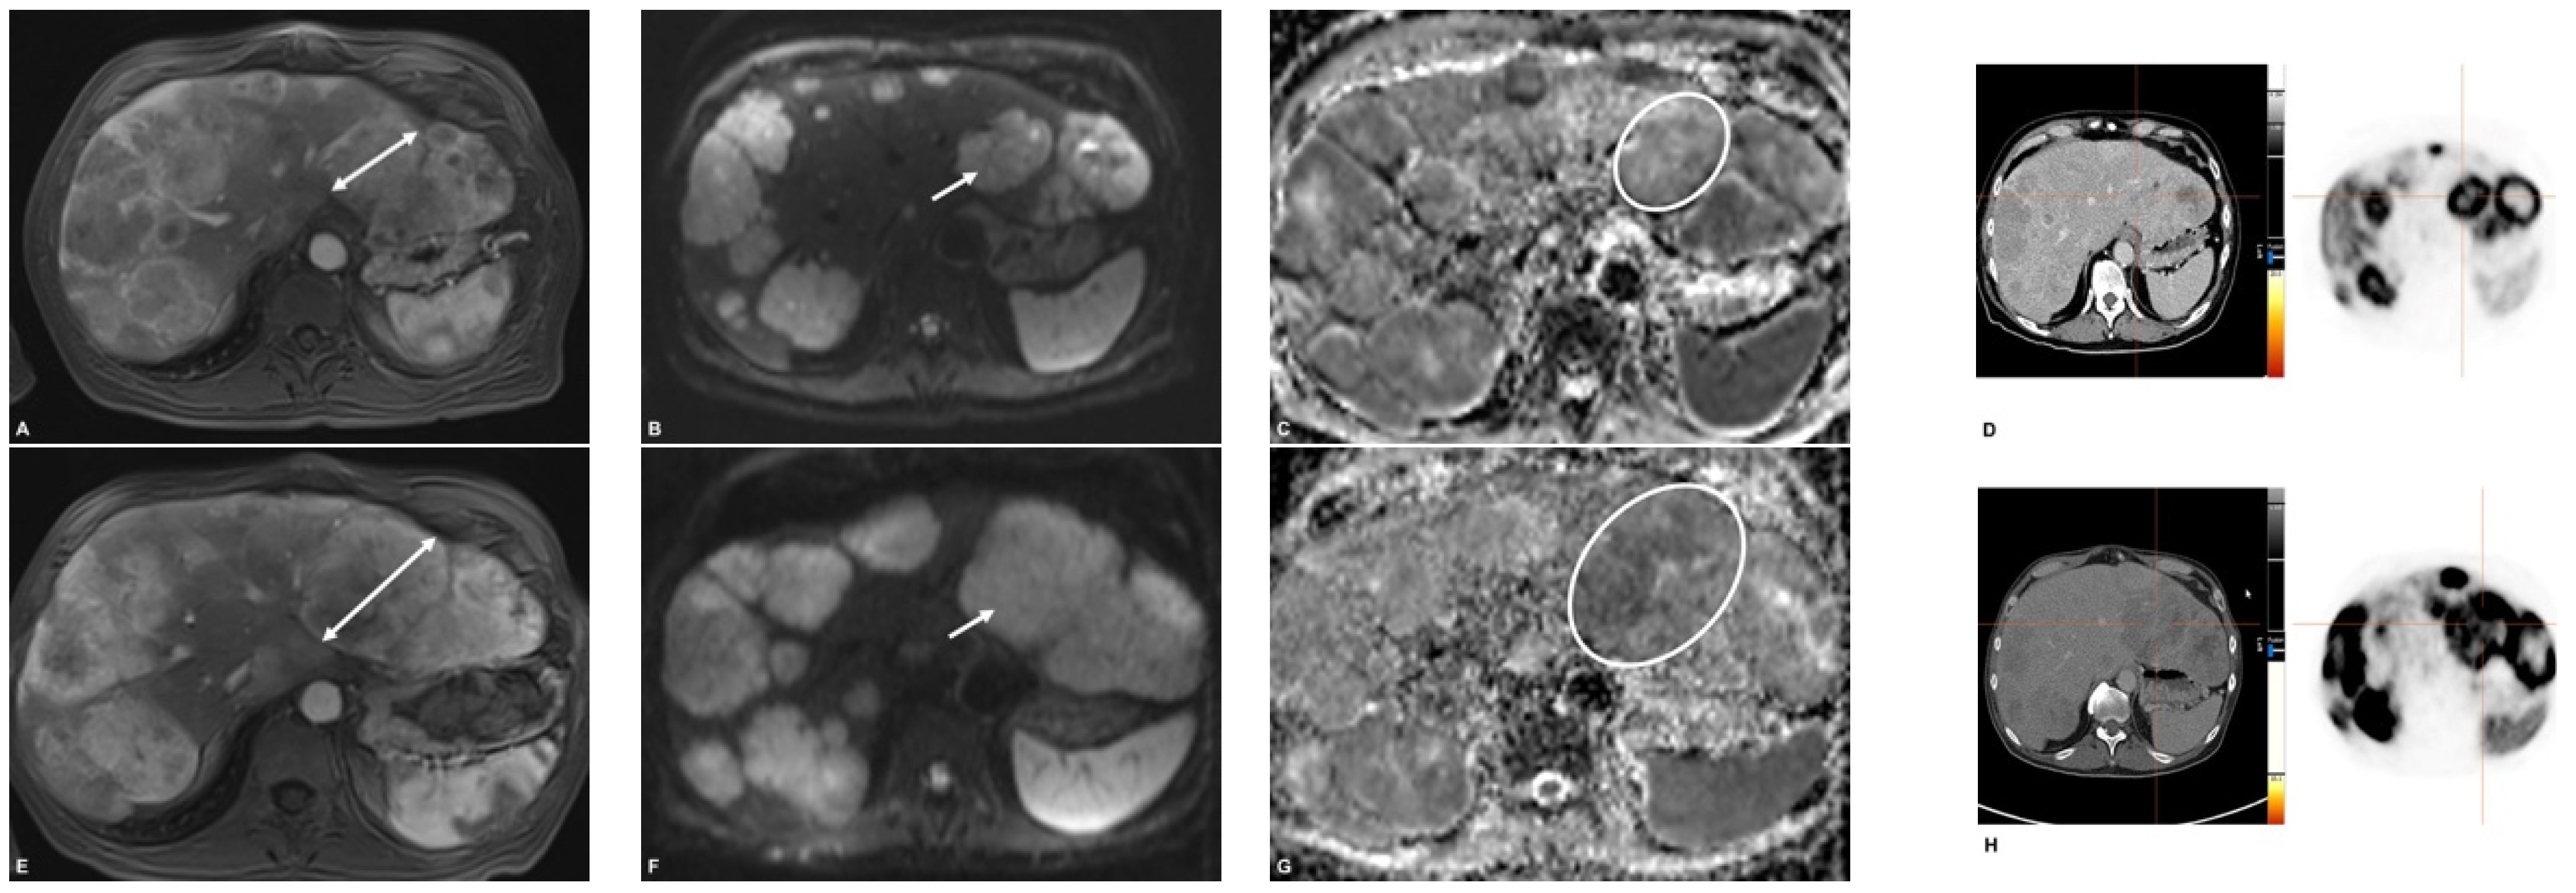

68Ga-DOTATATE PET/CT and MRI with Diffusion-Weighted Imaging (DWI) in Short- and Long-Term Assessment of Tumor Response of Neuroendocrine Liver Metastases (NELM) Following Transarterial Radioembolization (TARE)

2.3. MR Imaging

2.4. PET/CT

2.5. Image Analysis